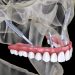

zygomatic-implants-advantages-and-zygomatic-implants-disadvantages

Zygomatic Implants Advantages and Zygomatic Implants Disadvantages